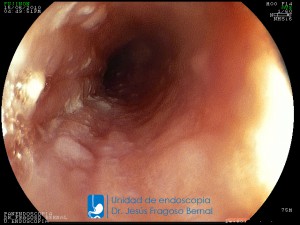

La Unidad de Endoscopía fue creada en 2002 por el Dr. Jesús Fragoso Bernal, es pionera en el estado por la utilización de la tecnología más avanzada, que nos permite ofrecer servicios integrales de diagnóstico y tratamiento para las enfermedades del aparato digestivo.